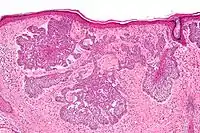

Nodular basal-cell carcinoma (also known as "classic basal-cell carcinoma") accounts for between 50% and 80% of all BCC.[2] It most commonly occurs on the sun-exposed areas of the head and neck.[2] Histopathology shows aggregates of basaloid cells with well-defined borders, showing a peripheral palisading of cells and one or more typical clefts.[17] Such clefts are caused by shrinkage of mucin during tissue fixation and staining.[18] Central necrosis with eosinophilic, granular features may be also present, as well as mucin. The heavy aggregates of mucin determine a cystic structure. Calcification may be also present, especially in long-standing lesions.[17] Mitotic activity is usually not so evident, but a high mitotic rate may be present in more aggressive lesions.[17] Adenoidal BCC can be classified as a variant of NBCC, characterized by basaloid cells with a reticulated configuration extending into the dermis.[17]

Cleft.